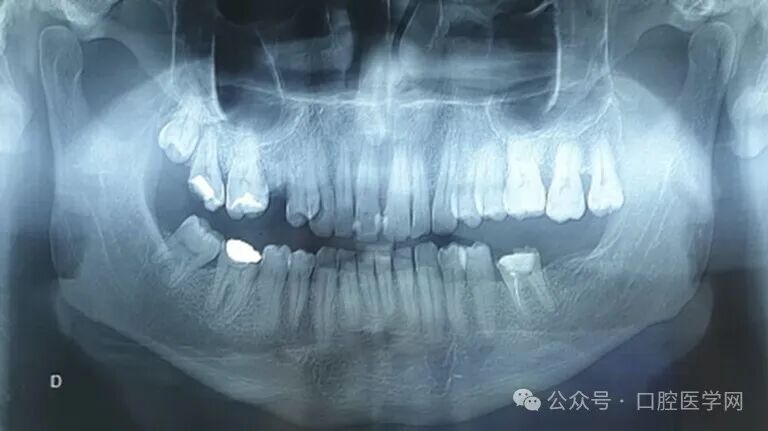

牙齿检查发现,患者的上颌中切牙出现松动,且左上中切牙的牙髓活力测试结果为阴性。X线片显示,上颌中切牙的牙周膜增宽,没有骨吸收迹象。全景片显示该区域无特异性病变(图2)。

图2

全景片显示上颌骨前上部有一处明显的边界不清的不透明区。